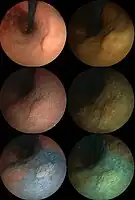

Endoscopic image of adenocarcinoma of duodenum seen in the post-bulbar duodenum..png.webp) Endoscopic image of gastric antral vascular ectasia seen as a radial pattern around the pylorus before (top) and after (bottom) treatment with argon plasma coagulation

Endoscopic image of gastric antral vascular ectasia seen as a radial pattern around the pylorus before (top) and after (bottom) treatment with argon plasma coagulation Endoscopic image of Barrett's esophagus, which is the area of red mucosa projecting like a tongue.